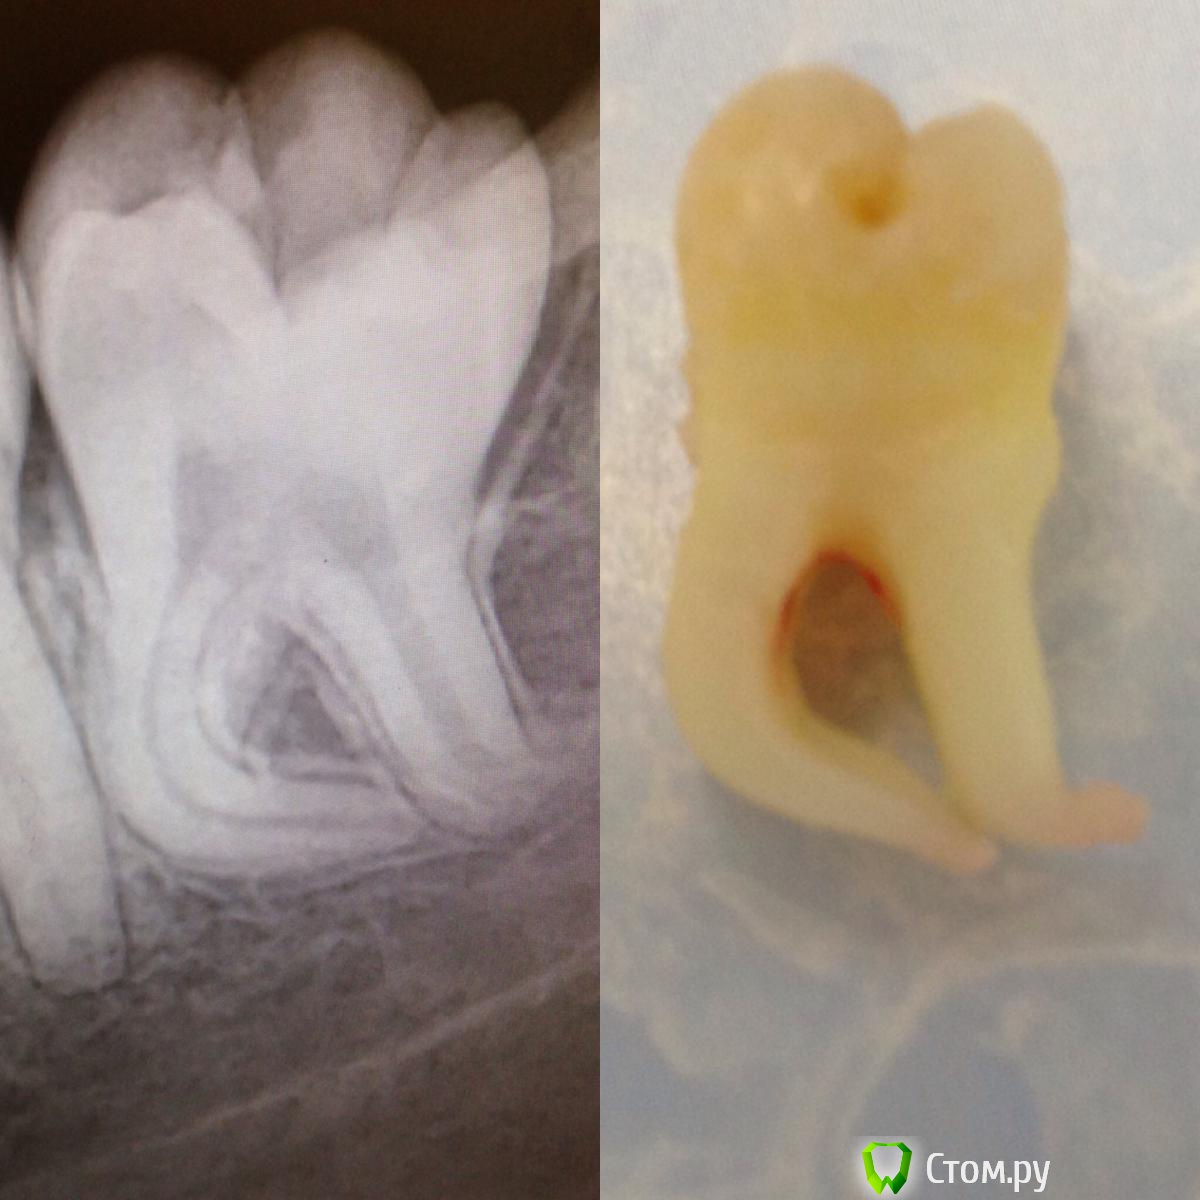

IvanK Опубликовано 10 декабря, 2013 Автор Поделиться Опубликовано 10 декабря, 2013 Разжиревшая годзила... Это шапка Петрушки, так назвала этот зуб ассистент )) 1 Ссылка на комментарий

komar56 Опубликовано 10 декабря, 2013 Поделиться Опубликовано 10 декабря, 2013 Это шапка Петрушки, так назвала этот зуб ассистент )) Не согласен! 1 Ссылка на комментарий